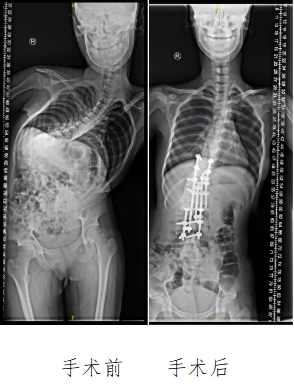

四年前,父母发现小王双肩不等高、背部隆起,当地医院诊断为脊柱侧凸。处在青春期的她恰在发育时期,脊柱侧弯程度进展迅速,逐渐呈夸张的“S”形弯曲,躯干胸廓严重变形,Cobb角近100度(≥10度为脊柱侧弯),导致呼吸不畅、间歇性剧痛,无法久坐或长时间行走,严重影响日常生活。更为严峻的是,若不及时手术干预,进行性加重的畸形将对她的心肺功能造成不可逆损伤,甚至存在脊髓受压导致瘫痪的风险。

手术团队利用数字化技术进行3D建模,精准定位截骨椎体、规划矫形方案,并反复推敲术中体位摆放、麻醉管理及神经监测预案,保障患者安全及矫形效果。在历时4个小时的手术中,团队逐步完成多节段松解、顶椎截骨,将扭曲的脊柱逐节矫正、复位,进行牢固固定。术后影像学检查显示,小王的脊柱形态得到显著矫正,躯干恢复平衡。

术后1周,小王已能在支具保护下逐渐下地站立行走。随着胸廓打开、心肺压迫解除,她的呼吸功能与生活质量获得了根本性改善。